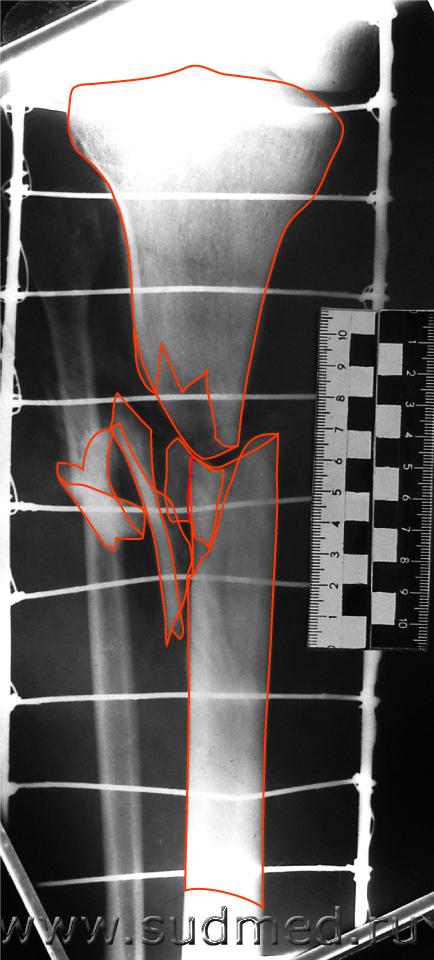

При возможности мы делаем так. Уважаемый Filin может конечно не согласиться и это его право.

Эскизы прикрепленных изображений

Судебная медицина - Прикрепленное изображение Судебная медицина - Прикрепленное изображение Судебная медицина - Прикрепленное изображение Судебная медицина - Прикрепленное изображение Судебная медицина - Прикрепленное изображение

А вот превращать трехмерное изображение в двухмерное (как это сделано Вами со снимком) - вряд ли можно расенить как удачное проведение экспертизы.

Главная проблема в СМ-рентгенологии - установление стороны и поверхности разрушения кости.

С десяток приспособлений придумано для этого ( в основном сетки или металлические стержни, помещаемые рядом с костью) и снимками её минимум в четырех проекциях.

А Вы берете одну (!) проекцию и сходу - реконструкция.